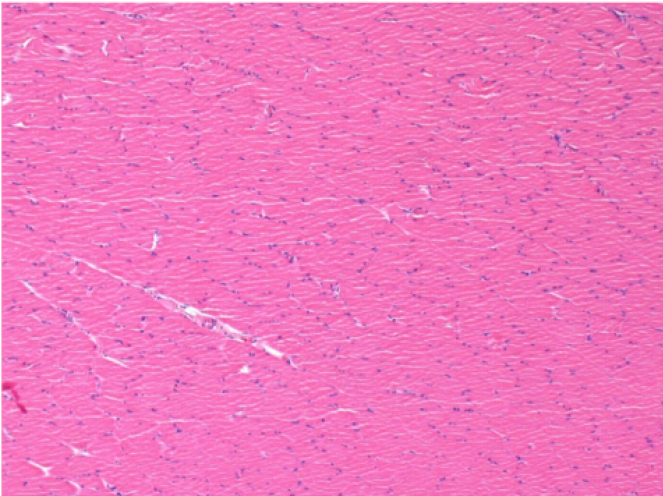

7 meses (D210) después de la inyección IM de Endopeel 0,1 ml en el músculo pretibial derecho.

Restitutio ad integrum (restauración a la condición original) completa después de 7 meses

L :Control 50xD210

R50X-D210